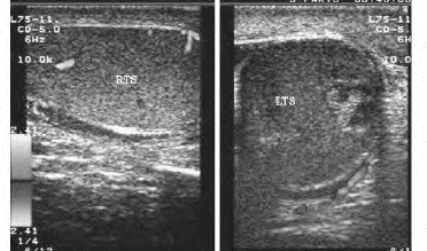

图31-6 睾丸扭转声像图(见彩图40)

右图为睾丸扭转,内回声低,分布不均匀,CDFI:内无血流信号;左图为对侧正常睾丸图像,CDFI:血流正常